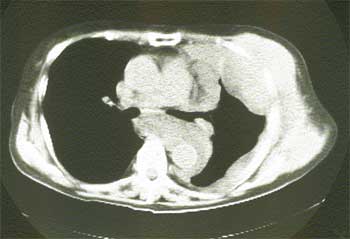

現在悪性胸膜中皮腫の診断として、まず胸部レントゲン写真を撮影し、その読影で異常な陰影が認められる場合に胸部CT写真が行われています。胸水が貯留していた場合は、細胞診の検査を外来で行う場合もあります。画像的に肺癌及び胸膜中皮腫が疑わしい場合に、通常検査入院を実施し、気管支鏡下気管支や肺の生検、胸腔鏡下胸膜生検及び肺生検を実施し病理学的診断を確定させています。悪性胸膜中皮腫の診断は容易でない時もあり、しばしば数ヶ月の経過観察後に中皮腫としての診断が確定される場合もあります。